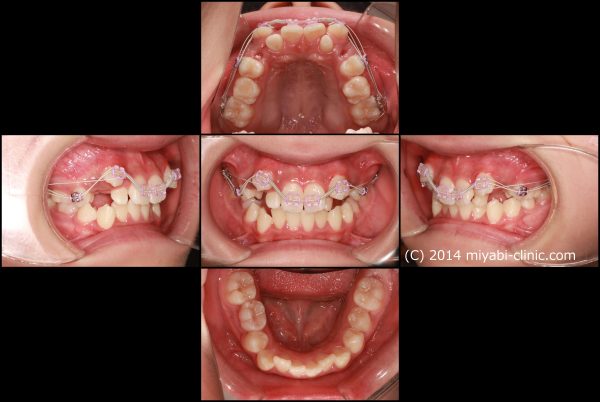

八重歯と 口もとを治すために上下顎左右の小臼歯抜歯を行い、前歯を整列しました。

2022年11月28日にスタートして 、2024年5月25日に 終 了 しました。

治療期間は19か月でした。

小臼歯の抜歯を行ったことで 犬歯の飛び出しが整い、

前歯は整列し八重歯はすっかりと解消しました。大きすぎた歯ならびが適正になりました。

上だけ注目されがちですが、下あごも前歯が整列し歯ならびが整いました。

また、前後的な距離が短くなり、適正な長さになりました。

上下の顎が適正な長さになった、この効果で上下の前歯が下がりました。

治療前後で前歯の傾斜、八重歯の飛び出しがかなり改善しました。